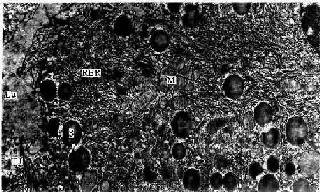

1.腺泡腺细胞呈锥体形,细胞底部位于基膜上,基膜与腺细胞之间无肌上皮细胞。腺细胞具有合成蛋白质的结构特点,基部胞质内含有丰富的粗面内质网和核糖体,故在HE切片上,此处胞质呈嗜碱性。细胞核圆形,位近基底部。细胞合成的蛋白质(酶的前体),经高尔基复合体组装于分泌颗粒(酶原颗粒)内。颗粒聚集于细胞顶部(图13-5),其数量因细胞功能状态不同而异,饥饿时细胞内分泌颗粒增多;进食后细胞释放分泌物,颗粒减少。

图13-5 小鼠胰腺细胞电镜像×12000

S分泌颗粒,RER粗面内质网,M线粒体,Lu腺腔,TJ紧密连接

(上海医科大学电镜室供图)